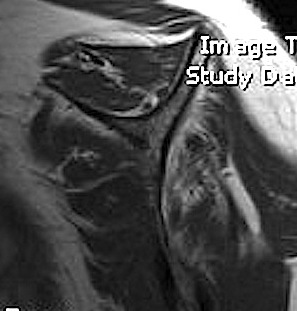

Full thickness rotator cuff tears

Partial bursal sided tear Partial articular sided tears

Small full thickness rotator cuff tear of supraspinatus - retracted to footprint

Large full thickness tear of supraspinatus and infraspinatus tendon - retracted to midhumeral head

Massive rotator cuff tear of the supraspinatus and infraspinatus tendon - retracted to glenoid